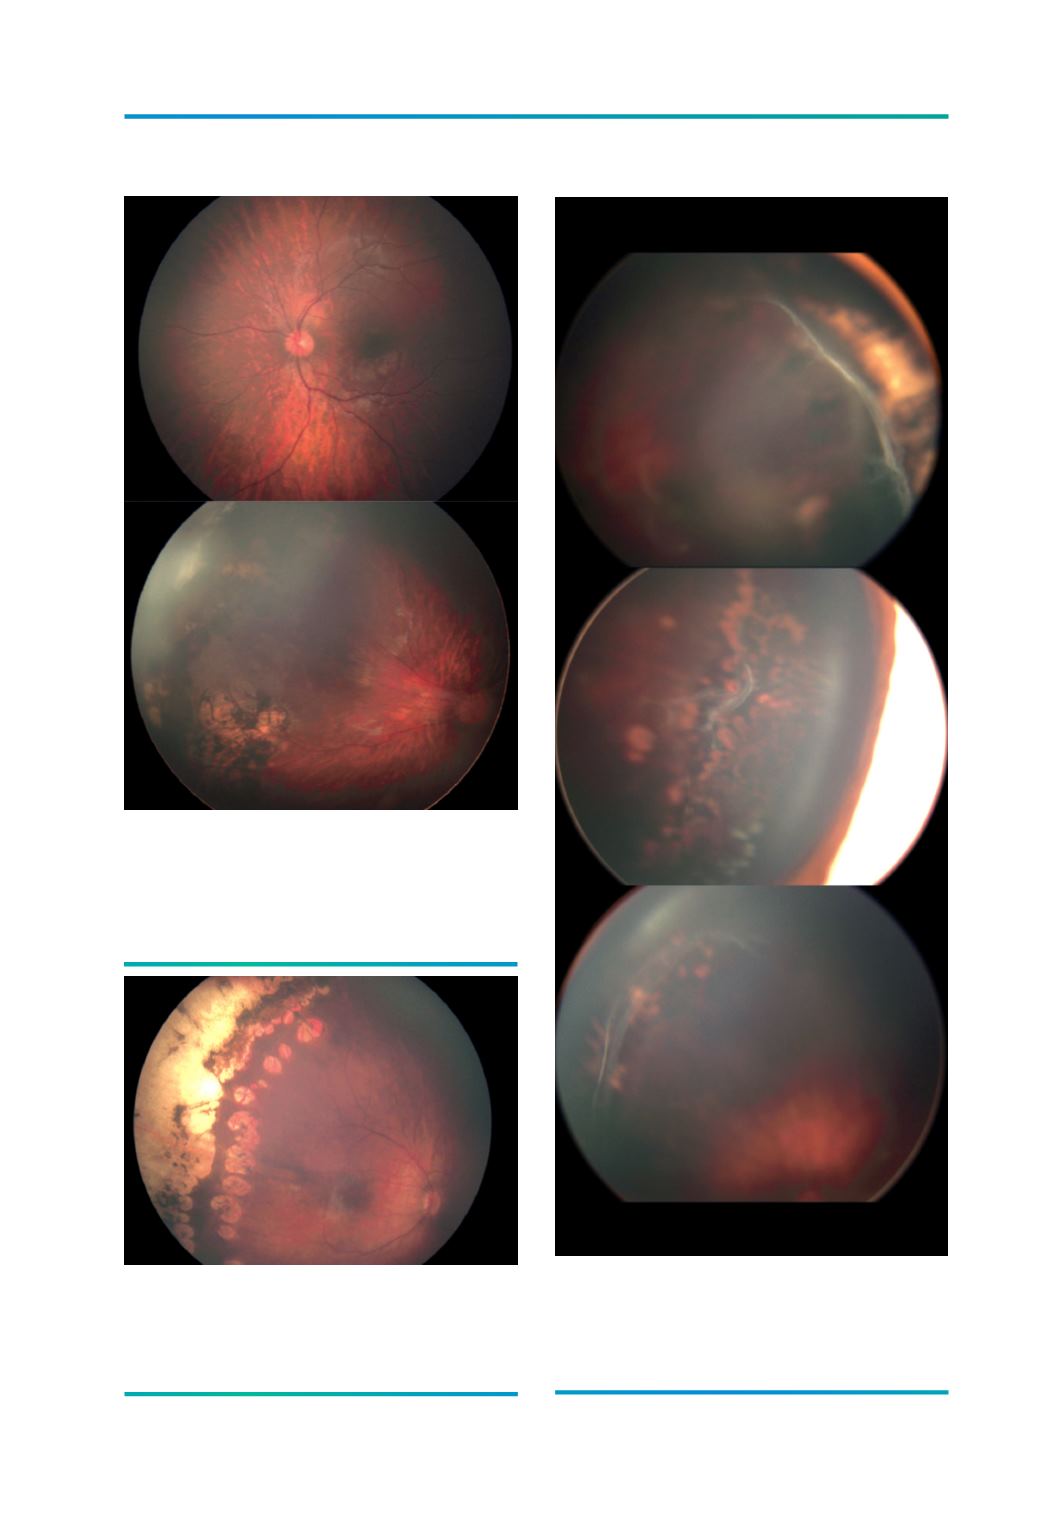

Figura 9.

Fundo ocular com normal angulação das arcadas

temporais (A) versus diminuição da angulação das

arcadas temporais com ectopia da mácula (B) por

contracção da proliferação temporal.

A

B